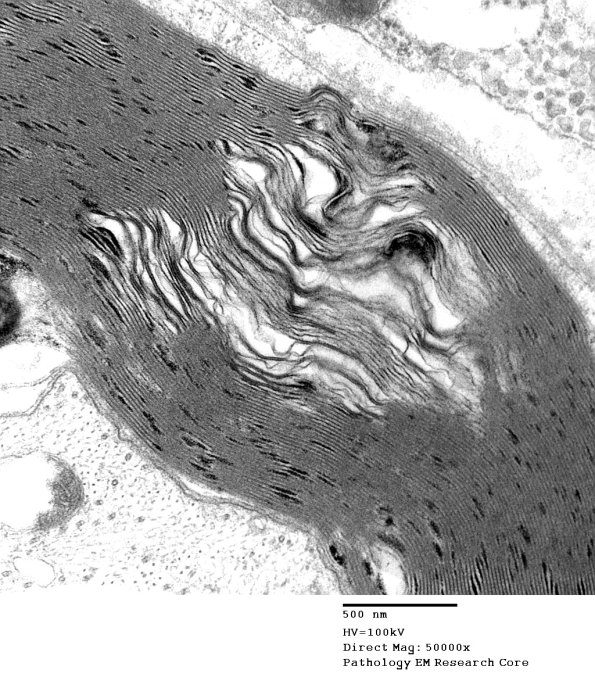

Washington University Experience | PERIPHERAL NEUROPATHY | 12 ANTI-MAG NEUROPATHY | 10A2 Artifact, separation myelin, Amiodarone (Case 10)_006a - Copy (2) - Copy

10A2 Artifact, separation myelin, Amiodarone (Case 10)_006a - Copy (2) - Copy

Higher magnification of image #10A1. (electron micrograph)